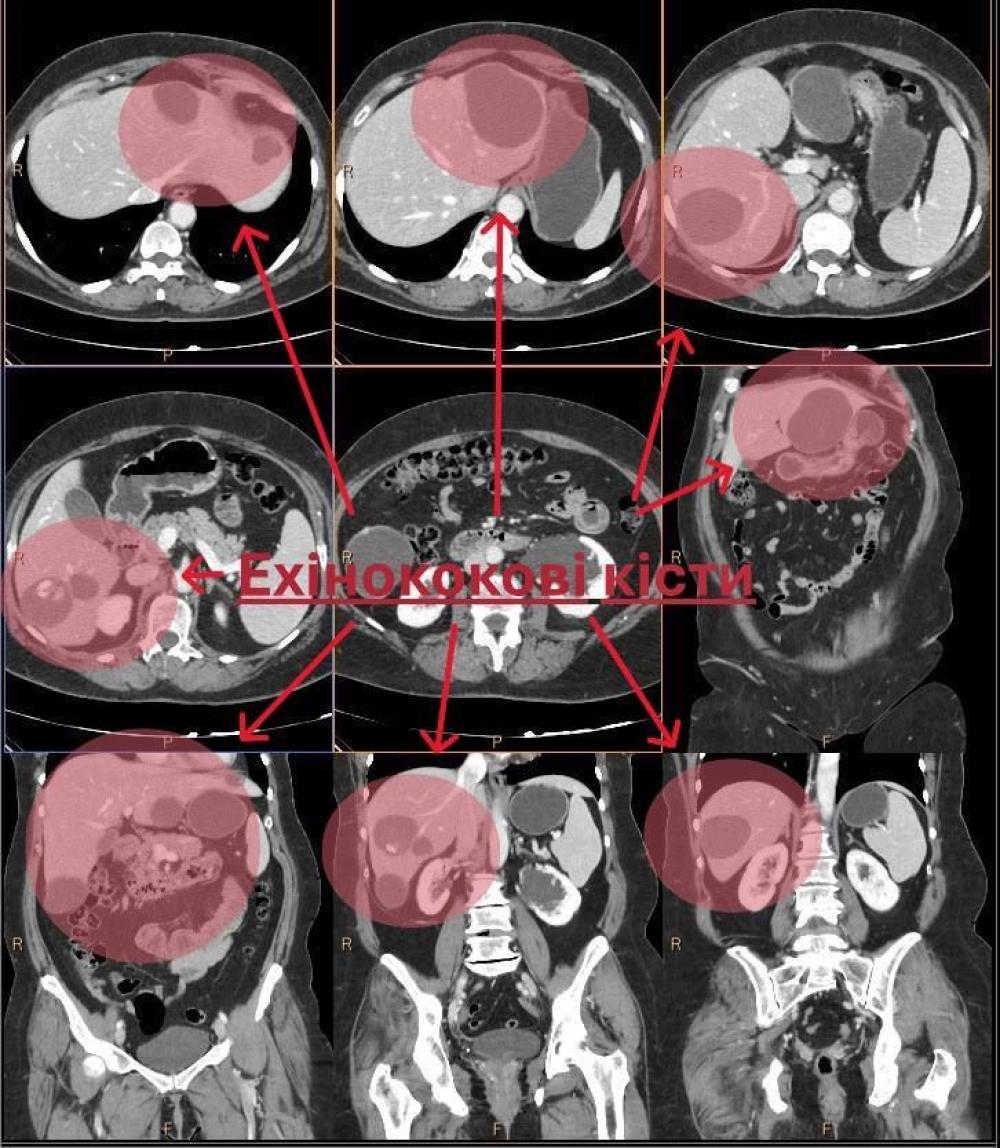

Лікарі Обласного центру планової хірургії та трансплантології РОКЛ імені Юрія Семенюка успішно провели операцію з видалення паразитарних новоутворень (ехінококових кіст) печінки.

До медиків звернулася жінка зі скаргами на загальну слабкість, підвищення температури, відчуття важкості та розпирання в правому підребер’ї та епігастрії. Після аналізу на ехінокок та комп’ютерної томографії у пацієнтки було виявлено множинні кісти. Єдиним способом лікування стало оперативне втручання.